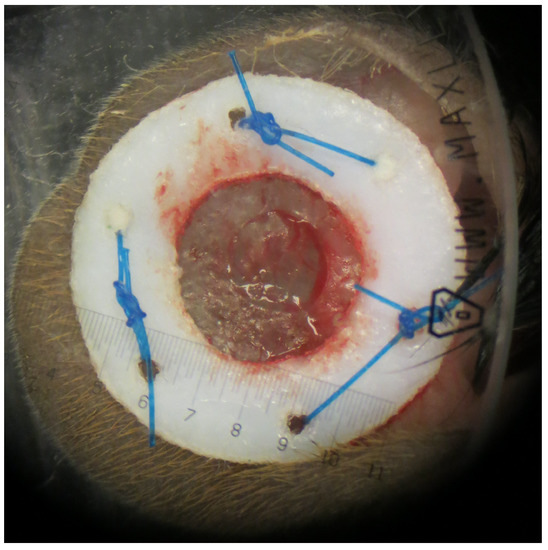

2.3. Murine Model of Wound Healing

2.4. OCT Imaging and Data Processing

2.5. Digital Measurement of Wound Size